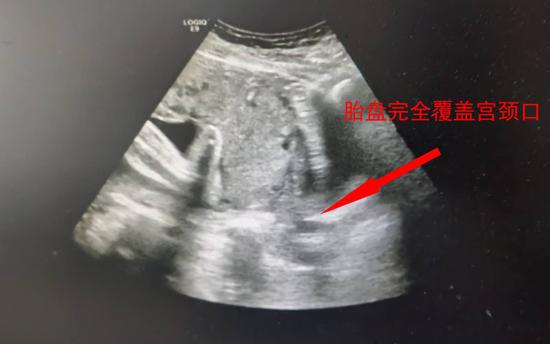

▲影像显示完全性前置胎盘

“胎膜早破、流水,胎盘完全覆盖宫颈内口,已经堵死了产道,更棘手的是出血还没有彻底止住……尽可能保胎延长孕周才好啊!”罗志平结合小王在外院的一些治疗,遂给予“解痉、预防感染和促胎肺成熟”等保胎治疗。虽说对症治疗后阴道出血量明显有减少,但未足月、出血时间长,胎膜早破、大人和宝宝的情况都不容乐观,随时可能因大出血危及母儿生命。小王正遭遇产科临床上最凶险的状况——完全性前置胎盘伴出血。